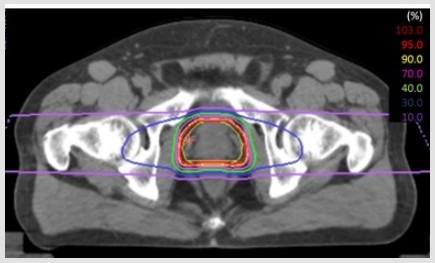

🔵線量分布のご紹介

以下が当院で実際に治療された患者さんの線量分布です。12回照射では、1日1方向ずつ、左右2方向から照射します。